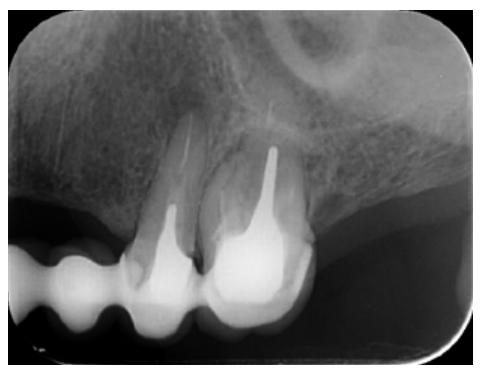

The patient provided an orthopantomography (OPG) as a radiological study (Figure 1). Periapical radiographs (Figures 2 and 3) were performed and a clinical examination including periodontal assessment of the affected teeth, without observing increased probing depths that could indicate the existence of endoperiodontal lesions.

To confirm the endodontic origin and the size of the lesions, tomographic examinations were performed with a slice thickness of 75 microns using CBCT CS8100 (Carestream Dental™), in which radiolucent periapical lesions were observed at the level of 12, 11, 21 (with bicortical involvement), 25 and vestibular roots at 26 (Figures 4 to 8).

The intracanal posts in the single-root teeth in our case, whose removal would have entailed the sacrifice of the scarce remaining tooth that could remain under the metal ceramic crowns, made us opt for periapical surgery on these teeth. However, tooth 26 was underfilled by several millimetres in the buccal roots and the CBCT showed an omitted MP canal, so we opted for nonsurgical root canal retreatment in this tooth.